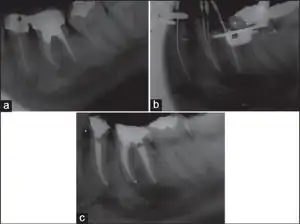

Endodontic periapical lesion-induced mental nerve paresthesia -a) before retreatment and approximation of mental foramen to apex of left mandibular b) working length radiograph c) after root canal filling

The nerve conduction study usually provides useful information for making diagnosis. A MRI or a CT scan is sometimes used to rule out some causes from the central nervous system.